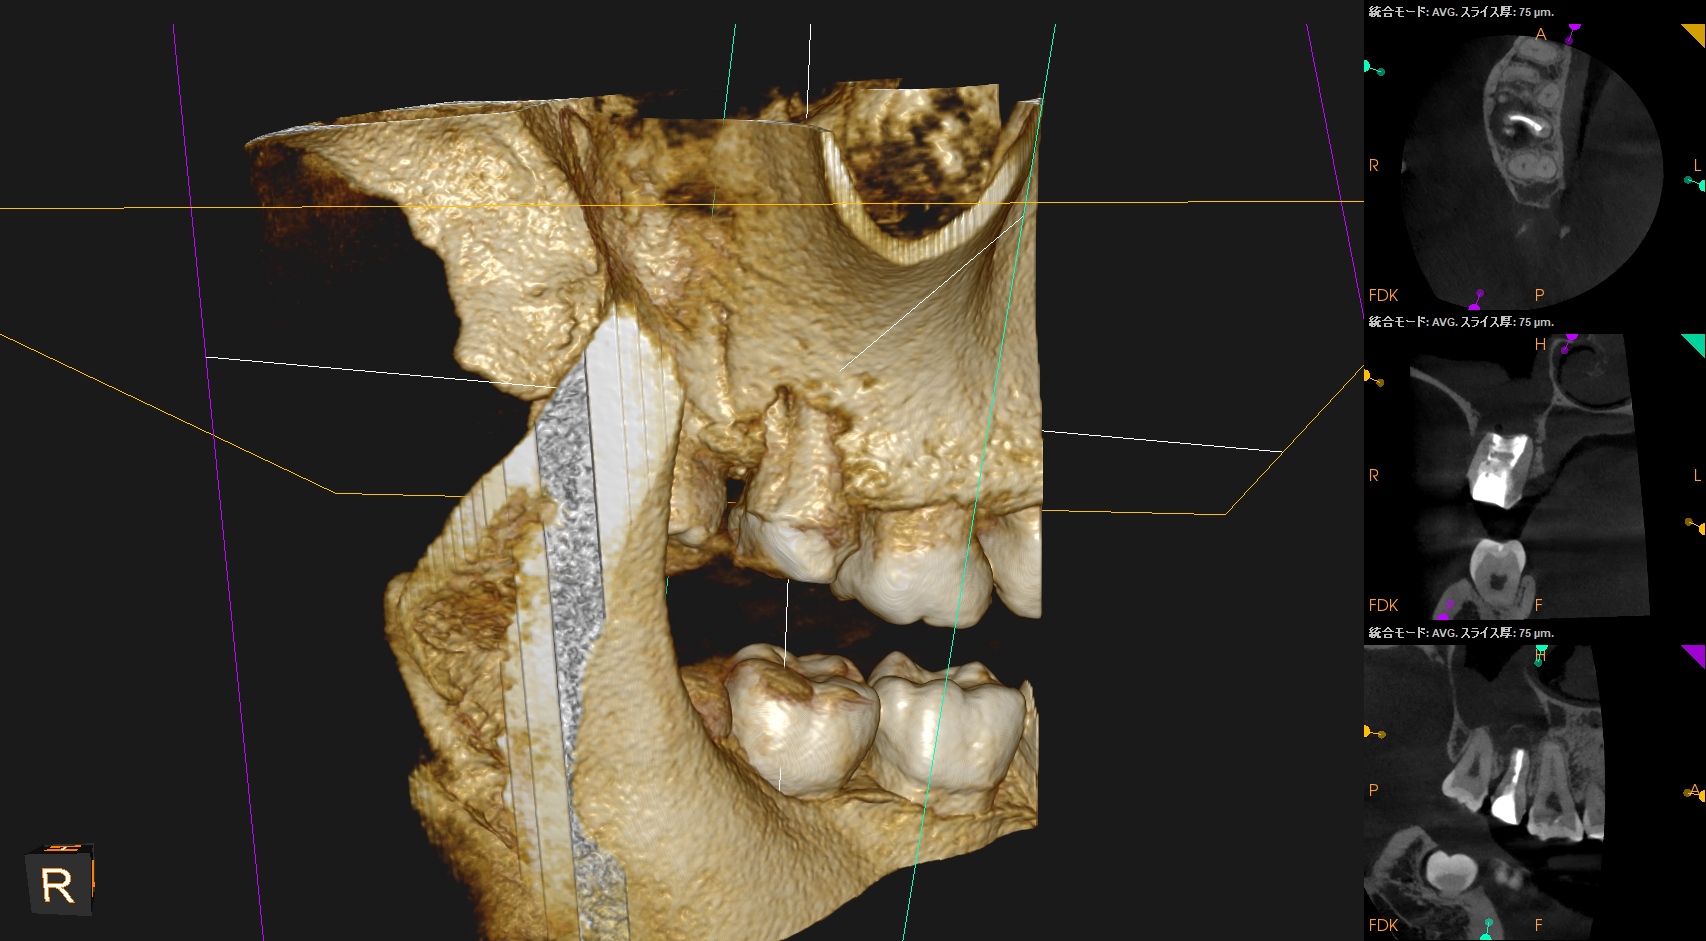

#2 Intentional Replantation(2025.11.11)

術後にPA, CBCTを撮影した。

MB

DB

P

B

次回は1ヶ月後である。